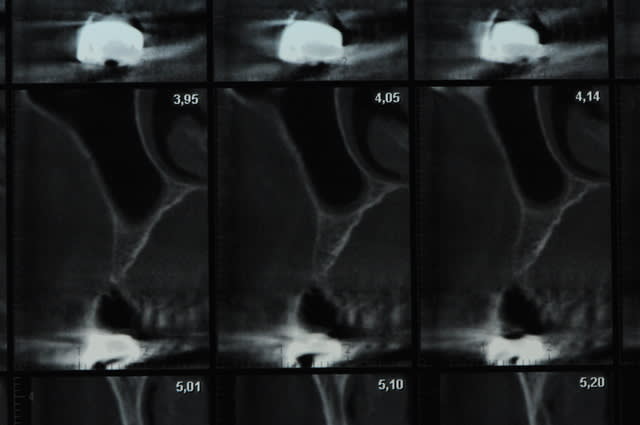

scanner...

aspect des crêtes et début du sinus lift.

l'os était tellement fin qu'il n'y avait presque pas besoin de la piezo.

piges de contrôle et pose des implants après 2 heures d'expansion au syndesmotome et ostéotomes!